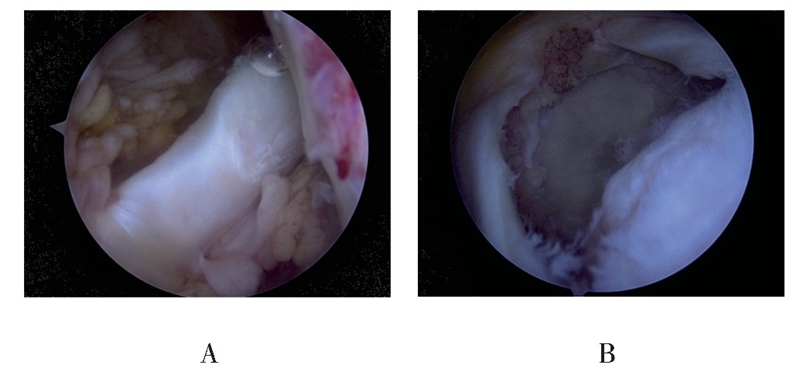

(1)首先外侧入路关节镜下观察评估肩袖撕裂及回缩情况,探查LHBT连续性及肌腱质量,术中确定肩袖为巨大撕裂,累及2根肌腱以上且冈上肌腱回缩明显,松解后仍难以拉回足印区或虽可拉回足印区,但张力较大,同时LHBT无明显撕裂或退变时,开始进行“Chinese Way”肩袖修补程序(见图1)。

图1 关节腔探查见LHBT连续性良好,无明显撕裂及严重退变(A);肩峰下间隙探查见后上方巨大肩袖撕裂,其中冈上肌腱回缩严重(B)